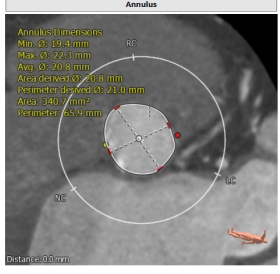

2020年10月12日,广东省人民医院迎来一位“特殊”的病人。病人是位68岁女性,初步诊断为二叶瓣畸形,主动脉瓣重度狭窄合并轻度二尖瓣反流。考虑到患者病情复杂,后续仍然存在冠脉介入治疗可能性,广东省人民医院罗建方教授团队共同讨论后,将目光移向了2020年6月通过国家药品监督管理总局(NMPA)批准上市的SAPIEN 3经导管主动脉瓣膜系统。

广东省人民医院心脏团队的这一想法是非常“大胆”的决定,与在国内已经广泛使用的自膨式TAVR瓣膜不同,SAPIEN 3瓣膜采用了球囊扩张式技术,为应对复杂且差异化大的心脏解剖结构提供了一种全新的选择。